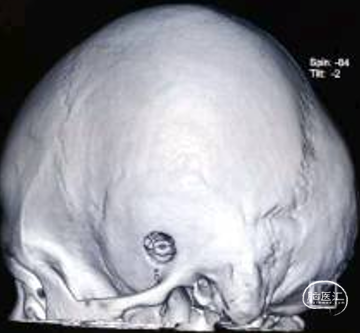

术中图片

颞骨钻孔,打磨内板使之成为“倒喇叭”状骨孔,Burr Hole外板内径11mm